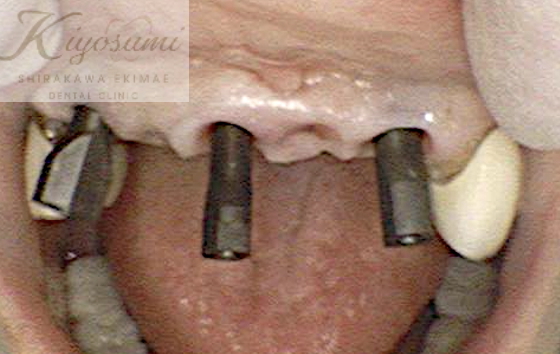

| 主訴 | 歯が揺れて噛めないので、噛めるようにして欲しい。 |

| 治療内容 | 基本的な歯周病治療、根の治療を実施し、歯の高さが足りない箇所は歯冠長延長術、保存が難しい歯は一部歯根分割抜去を行いました。欠損部はインプラントを用いず、ジルコニアブリッジで仕上げています。 |

| 想定されたリスク | ※残存している歯の本数が少ないため、残っている歯だけでブリッジを行うには長期予後が見込めない可能性があり、患者さんにご理解をいただいたうえで被せ物を行っています。 ※歯周病治療や根の治療をしても歯を残せない可能性がありました。 |